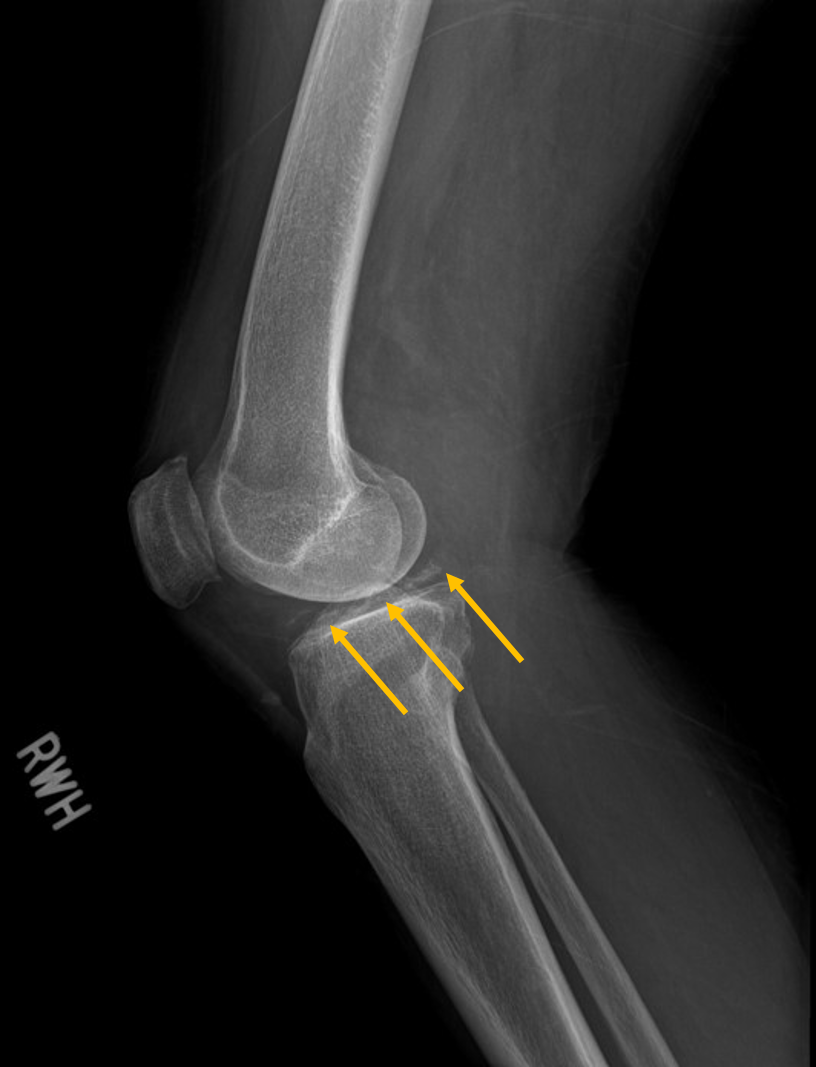

X ray image showed chondrocalcinosis over triangular fibrocartilage complex (TFCC) of right wirst (yellow arrow in Picture 2) and right knee (Picture 3). Asymmetrical joint space narrowing with spur formation (white arrow in Picture 4) of right knee was seen, compatible with OA change. No fracture or joint erosion seen over right elbow. (Picture 5).

Picture3 Right Knee Lat. view